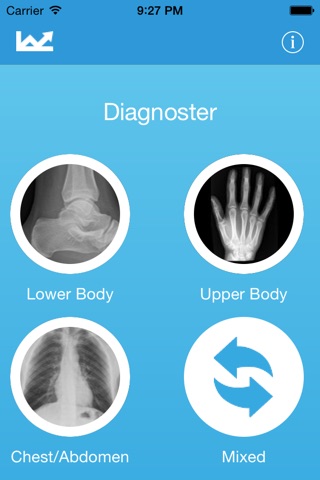

Diagnoster is composed of a series of short ‘packets’ of images, with each packet containing x-rays around the three main topics of ‘Upper Limbs’, ‘Lower Limbs’ and ‘Chest/Abdomen’. The Shuffle button randomly generates a packet based on a selection of images from all parts of the body.

Images grouped by topic but can also be mixed for increased difficulty